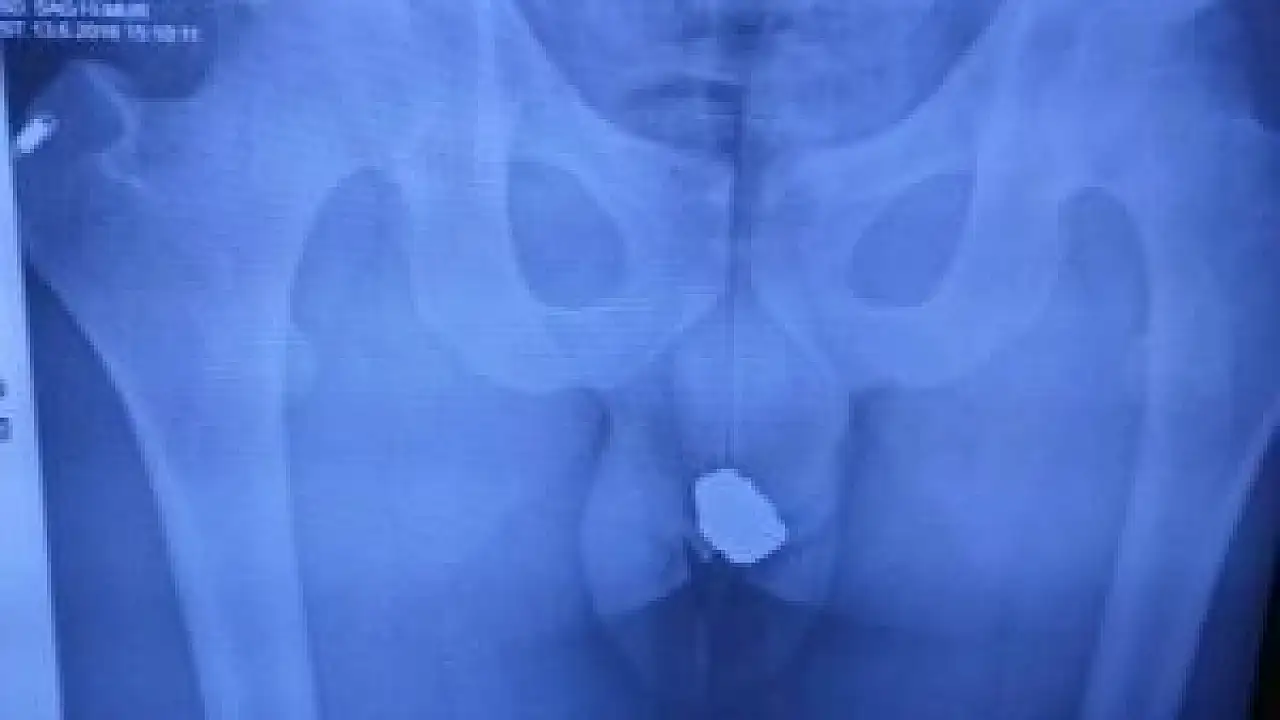

Otomobil İlçe Emniyet Müdürlüğü’nde parka çekilirken araçta yapılan aramada adreslerden çalınan cep telefonu ve gözlük de bulundu. Emniyet Müdürlüğü’ndeki sorgusunun ardından sağlık kontrolü için Beyşehir Devlet Hastanesi’ne götürülen Ö.A.’nın (24) yürüyüşündeki aksamadan şüphe eden polis ekipleri hastanede şahsın röntgen filmini de çektirdi. Çekilen röntgen filmi sonucu, şüphelinin adreslerden çalınan 3 altın yüzük, 4 adet küpe ve 2 adet yonca şeklindeki küçük altın kolyeyi makatında sakladığı ortaya çıktı.

Şüphelinin yüzük, kolye ve küpeleri bir naylon içerisine koyduktan sonra çakmak ateşiyle vakumlayarak makatına yerleştirdiği belirlendi. Röntgen filmi sonucunda, “Bu nedir’ sorusu sorulan şüphelinin, “küçükken yuttuğum taş” diye cevap verdiği, arama yapılacağının söylenmesi üzerine kendiliğinden çıkararak polise verdiği öğrenildi.